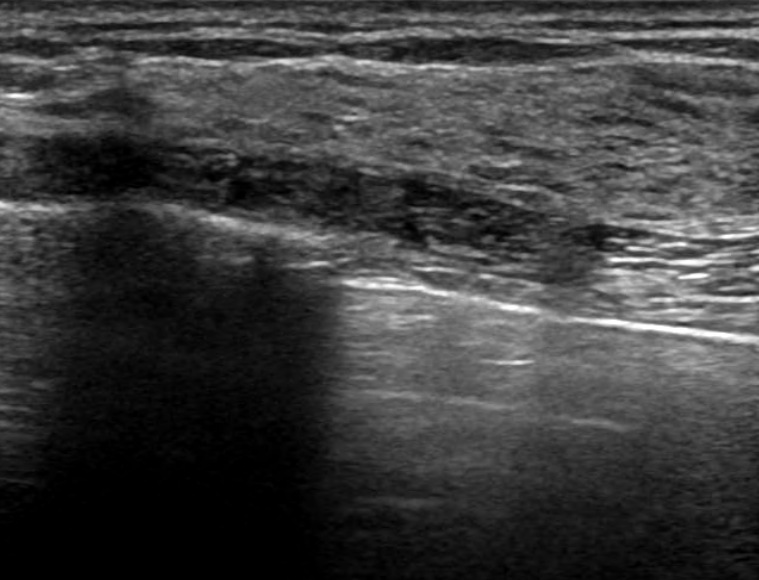

엑스레이만으로는 암을 찾기 어렵기 때문에 다른 검사 방법을 함께 사용하는 것이 좋습니다. 일반적으로는 유방 초음파 검사를 많이 하고 있습니다. 초음파는 유방의 단단한 조직과 종양을 더 잘 구분할 수 있습니다. 그리고 필요시에는 MRI 검사를 할 때도 있습니다.

○ 유방 초음파 검사: 초음파는 치밀유방에서도 조직을 잘 구분할 수 있어서 정확성이 높습니다. 다만 암과 관련이 있는 미세석회화는 발견이 어려울 때가 있어서, 유방촬영술과 같이 하는 것이 좋습니다.